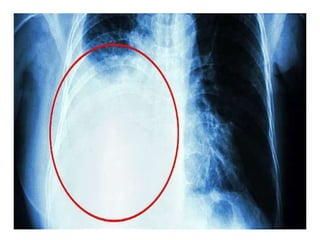

 Radiological examination

• X-ray chest PAview done in erect position-a total of

300mL of fluid is needed to diagnose pleural effusion

clinically and radiologically

• Even 50mL of fluid can be demonstrated radiologically in

lateral decubitus

Findings

• Obliteration of cardiophrenic and costophrenic angles

• Loculated effusions

• Subpulmonic effusion-collection of fluid below the

diaphragm will lead to elevation of diaphragm, confirmed

by X-ray in lateral decubitus

• Lateral decubitus on side of effusion will show a shift in

the fluid level

• Tracheal and mediastinal shifts are seen in massive

effusion